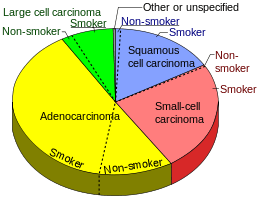

Lung cancers are classified according to histological type.[12] This classification is important for determining management and predicting outcomes of the disease. Lung cancers are carcinomas—malignancies that arise from epithelial cells. Lung carcinomas are categorized by the size and appearance of the malignant cells seen by a histopathologist under a microscope. For therapeutic purposes, two broad classes are distinguished: non-small-cell lung carcinoma and small-cell lung carcinoma.[65]

The three main subtypes of NSCLC are adenocarcinoma, squamous-cell carcinoma and large-cell carcinoma.[6]

Nearly 40% of lung cancers are adenocarcinoma, which usually originates in peripheral lung tissue.[12] Although most cases of adenocarcinoma are associated with smoking, adenocarcinoma is also the most common form of lung cancer among people who have smoked fewer than 100 cigarettes in their lifetimes ("never-smokers")[6][66] and ex-smokers with a modest smoking history.[6] A subtype of adenocarcinoma, the bronchioloalveolar carcinoma, is more common in female never-smokers, and may have a better long-term survival.[67]

Squamous-cell carcinoma accounts for about 30% of lung cancers. They typically occur close to large airways. A hollow cavity and associated cell death are commonly found at the centre of the tumor.[12] About 9% of lung cancers are large-cell carcinoma. These are so named because the cancer cells are large, with excess cytoplasm, large nuclei and conspicuous nucleoli.[12]

From the 1960s, the rates of lung adenocarcinoma started to rise relative to other types of lung cancer. This is partly due to the introduction of filter cigarettes. The use of filters removes larger particles from tobacco smoke, thus reducing deposition in larger airways. However, the smoker has to inhale more deeply to receive the same amount of nicotine, increasing particle deposition in small airways where adenocarcinoma tends to arise.[155] The incidence of lung adenocarcinoma continues to rise.[156]